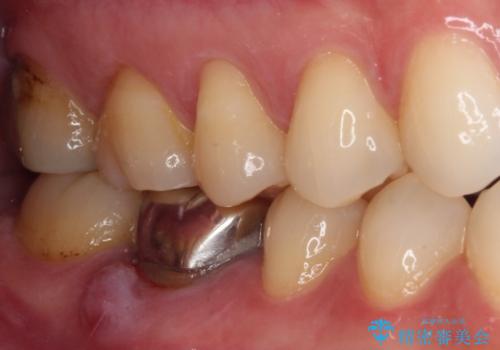

- 右下の奥歯の歯茎が腫れているとのことで来院された患者様です。

銀のクラウンが装着されていた歯は根管治療が必要であり、その奥の歯は大きな詰め物の隙間が虫歯になってしみていました。

根管治療などを行った後に、オールセラミッククラウンにて補綴することとしました。